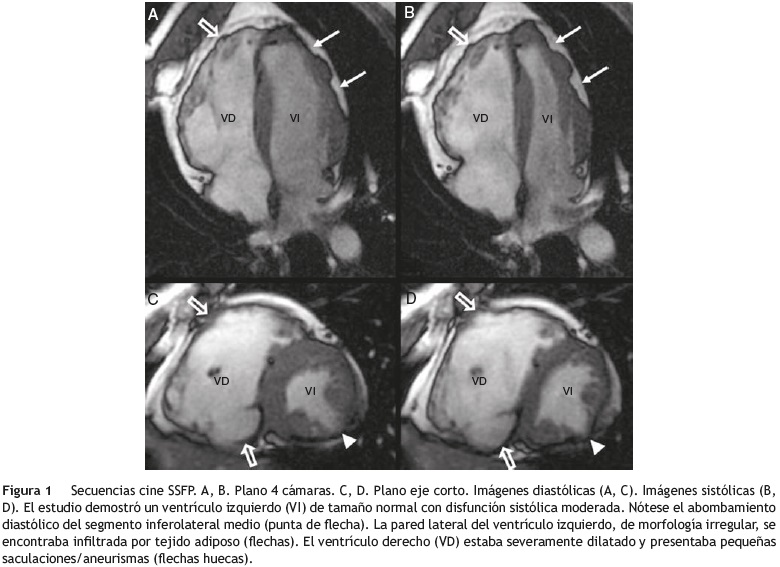

El estudio de CRM se llevó a cabo con un protocolo convencional que incluía secuencias anatómicas del tórax, secuencias cine eco de gradiente steady-state free precession (SSFP) en los planos 4 cámaras, eje corto y tracto de salida del ventrículo izquierdo, perfusión en reposo y secuencias de realce precoz y realce tardío tras la administración intravenosa de contraste paramagnético3. La CRM puso de manifiesto un ventrículo izquierdo de tamaño

normal con disfunción sistólica moderada (FE = 35%), acinesia del segmento inferior medio y discinesia y abombamiento diastólico del segmento inferolateral medio. Los grosores miocárdicos eran normales excepto en el segmento inferolateral medio, que se encontraba muy adelgazado (6mm). La pared lateral del ventrículo izquierdo mostraba una morfología irregular y se encontraba infiltrada por tejido adiposo (fig. 1). El ventrículo derecho estaba dilatado (volumen telediastólico ajustado por superficie corporal de 147ml/m2, volumen telesistólico ajustado por superficie corporal de 111 ml/m2) y presentaba una función sistó-lica severamente deprimida (FE = 25%). Morfológicamente había áreas de adelgazamiento de la pared. El análisis de la contractilidad segmentaria de este ventrículo mostró movimiento disincronía del septum, disincronía de la contracción ventricular, segmentos acinéticos y discinéticos y formación de pequenñas saculaciones/aneurismas (fig. 1). Durante la perfusión en reposo se observaron trombos endocavitarios en los ápices de ambos ventrículos. En fases tardías se objetivó realce de las caras anterior e inferior del ventrículo derecho y de los segmentos inferior medio, inferolateral medio y ápex del ventrículo izquierdo, con una distribución predominantemente sube-picárdica (fig. 2). Ante estos hallazgos, el estudio de CRM se consideró compatible con miocardiopatía arritmogénica del ventrículo derecho con afectación del ventrículo izquierdo.